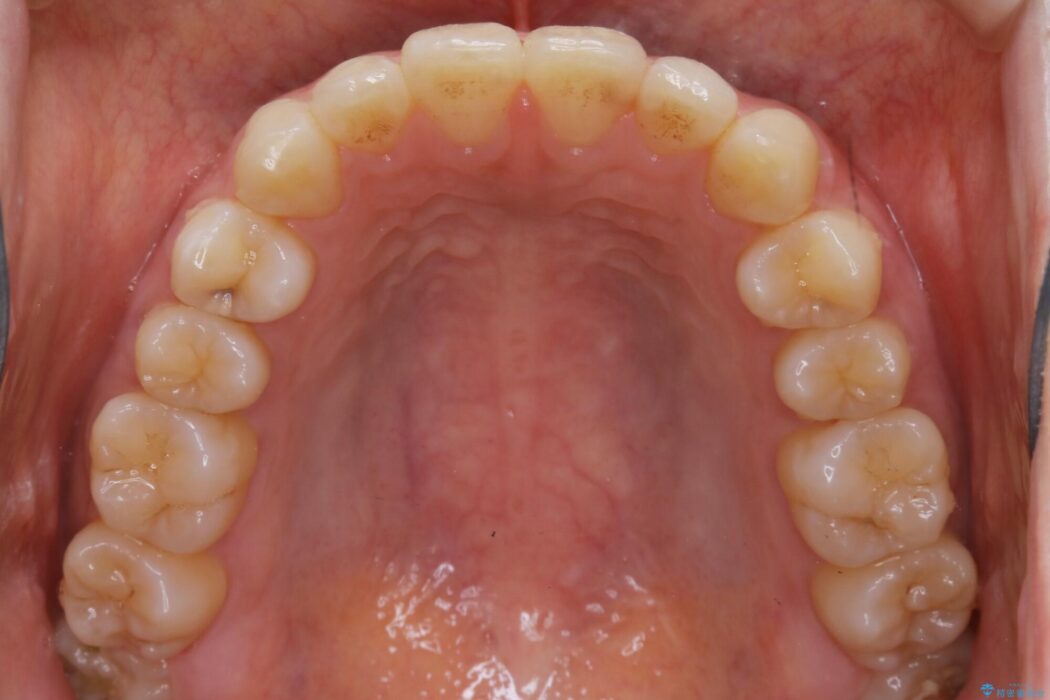

下額前歯が少しガタついていることを気にされて来院されました。

検査をしたところ奥歯の噛み合わせなどに問題が見られなかったため、軽度のねじれがある下顎前歯に焦点を当てた部分矯正の適応が可能と判断し、インビザラインのライトパッケージをご提案しました。